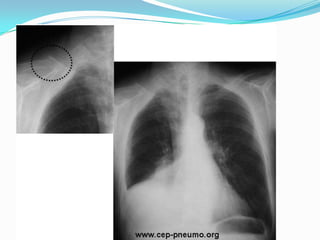

Pneumothorax PNO:  Dllatérothoracique, brutale, spontanée ou post traumatique, en coup de poignard, augmentée par inspiration profonde et toux, accompagnée de dyspnée  Dg évoqué par examen clinique qui met en évidence tympanisme et diminution voire silence auscultatoire.  Radio pul confirme le Dg: hyperclarté partielle ou totale.  Le trt est l’excuflation en urgence voire drainage thoracique